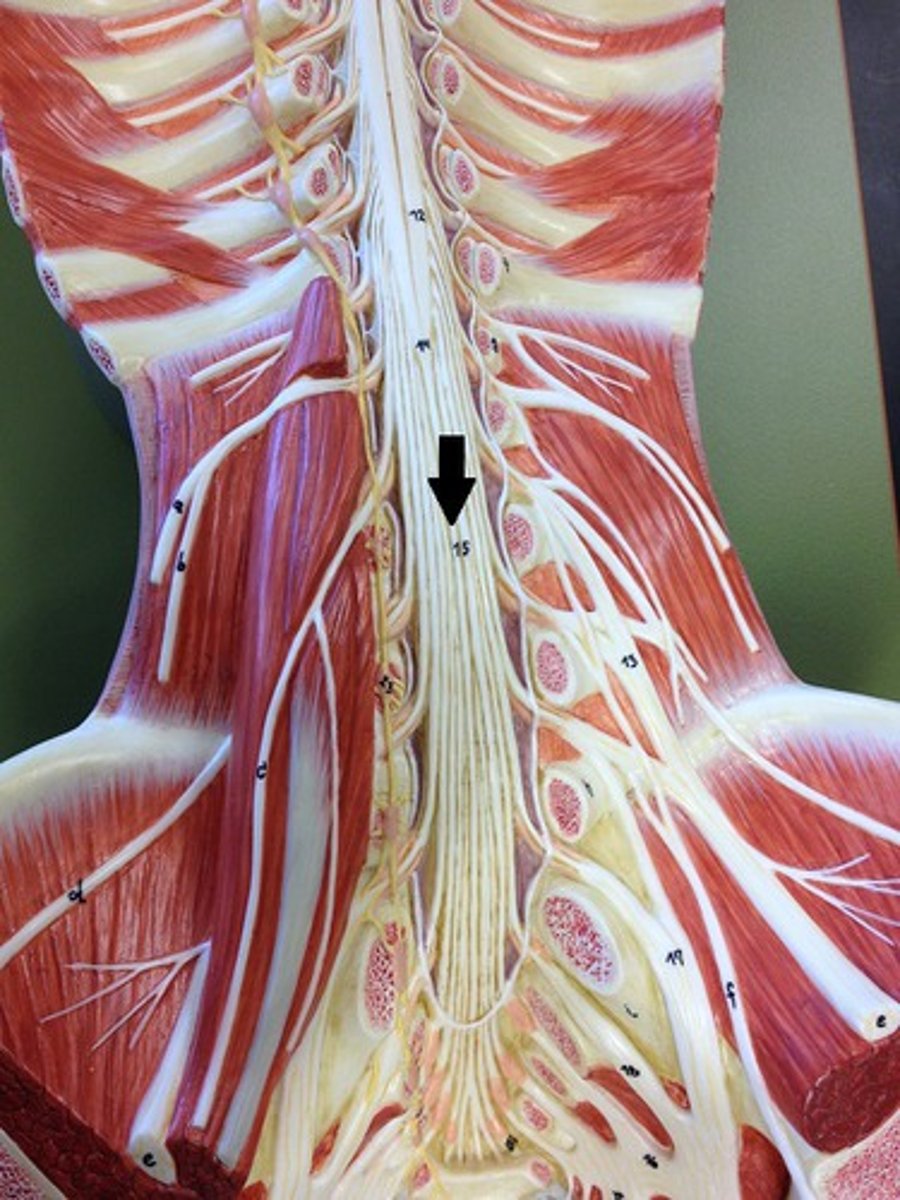

filum terminale

single thin thread of fibrous tissue at end of conus medullaris in the center that attaches to coccygeal ligament

posterior root

axons of sensory neurons

posterior root ganglion

anterior root

axons of motor neurons

spinal nerve

cauda equina

bundle

cervical plexus

C1-C5

brachial plexus

C5-T1

lumbar plexus

T12- L4

sacral plexus

L4- S4